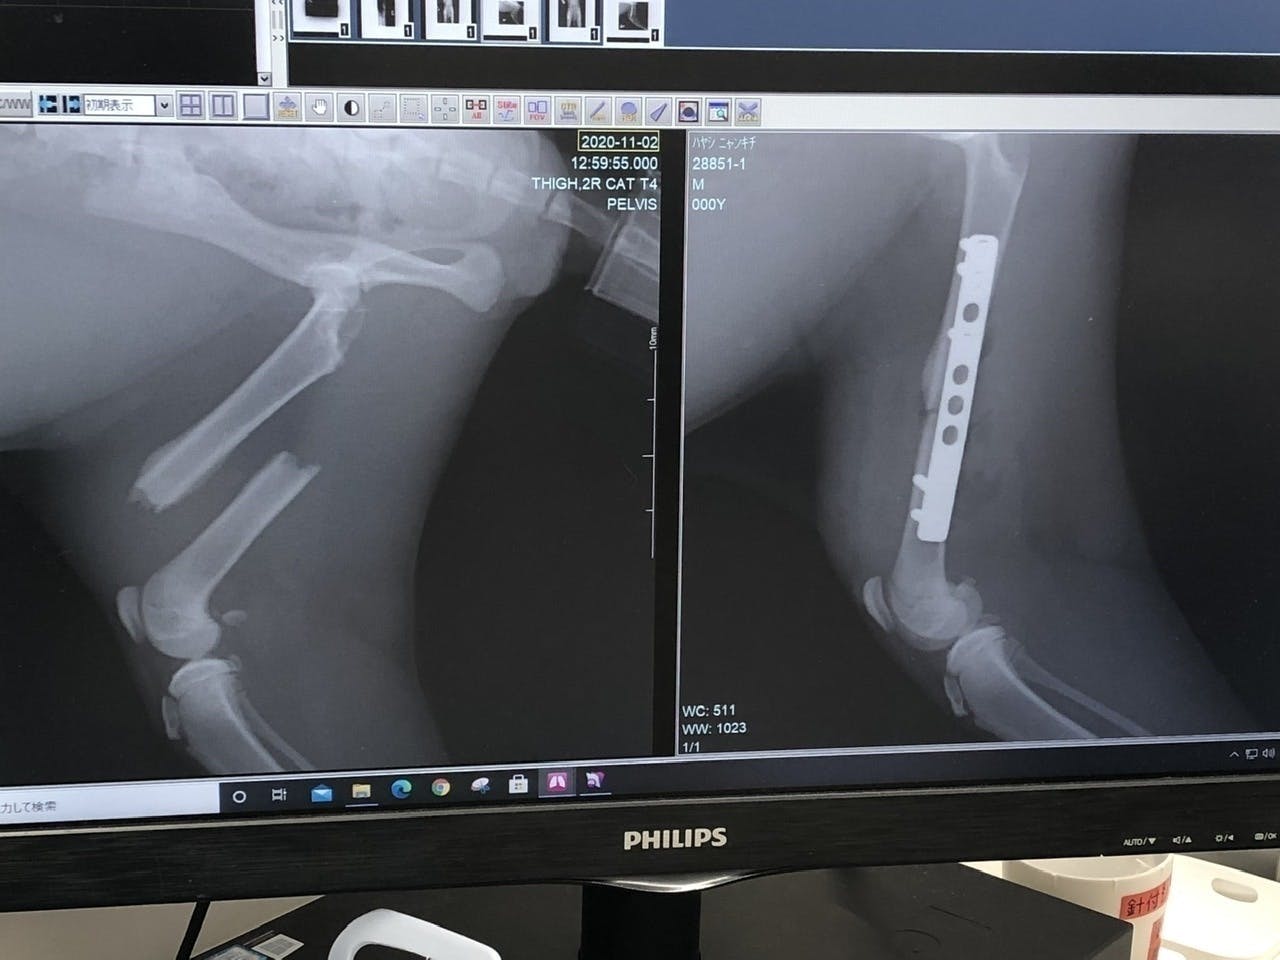

11月30日(月)今日は抜糸後から2週間が経ち、2回目のレントゲン写真を撮りました!だいぶ筋肉も発達し、骨も固定されてまして順調です。最近では、かなり走り回る様になり、保護した当初の事を考えると、見違えるように元気になりました!今後の予定としては…◎2回目のワクチン→◎最後のレントゲン→◎避妊手術の流れになります。クラウドファンディングは12月15日まで続きます。最後まで頑張ります!